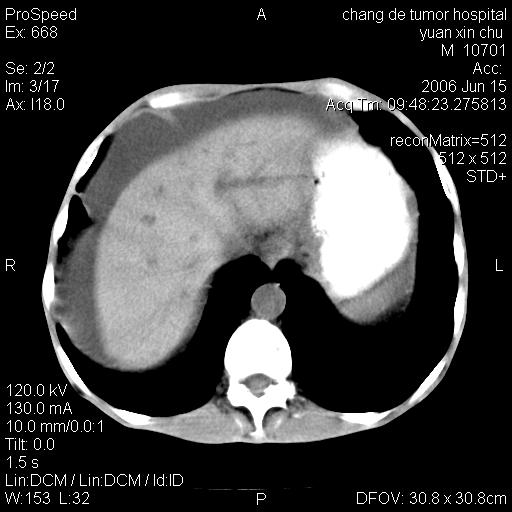

以下是引用qian在2007-4-23 19:06:00的发言:[br]胰腺体积增大,轮廓欠规则,肝轮廓波浪状改变,肝裂增宽,肝周、脾周有液性密度,腹膜后肿大淋巴结,考虑1、胰腺癌伴腹膜后淋巴结转移;2、肝硬化伴腹水。

以下是引用卜一在2007-4-23 20:12:00的发言:[br]胰腺体积增大,轮廓欠规则,肝轮廓波浪状改变,肝裂增宽,肝周、脾周有液性密度,腹膜后肿大淋巴结,考虑1、胰腺癌伴腹膜后淋巴结转移;2、肝硬化伴腹水。支持!